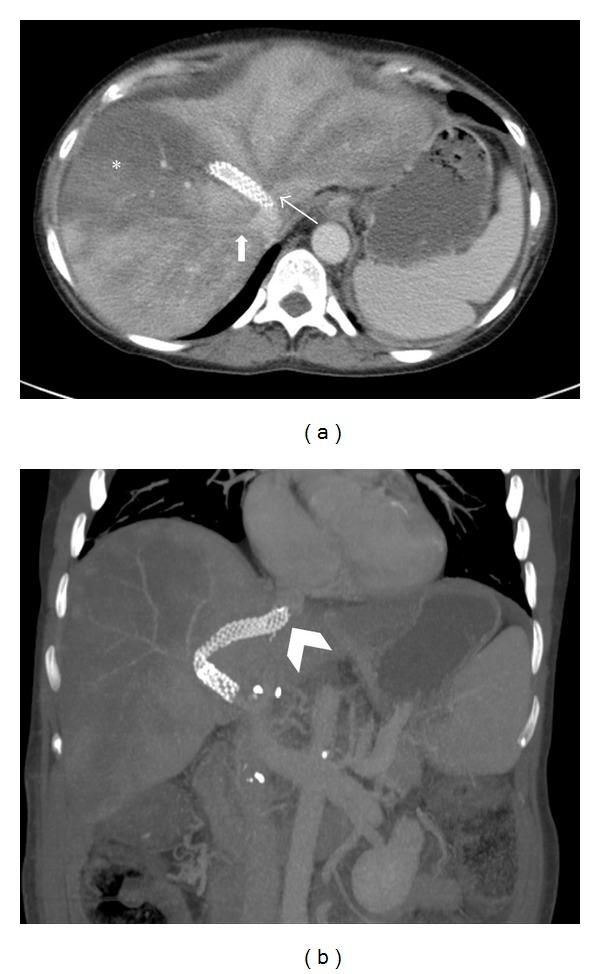

Budd-Chiari syndrome refers to hepatic pathology secondary to diminished venous outflow, most commonly associated with venothrombotic disease. Clinically, patients with Budd-Chiari present with hepatomegaly, ascites, abdominal distension, and pain. On imaging, Budd-Chiari syndrome is hallmarked by occluded IVC and or hepatic veins, caudate lobe enlargement, heterogeneous liver enhancement, intrahepatic collaterals, and hypervascular nodules. Etiopathological factors for Budd-Chiari syndrome include several systemic thrombotic and nonthrombotic conditions that can cause venous outflow obstruction at hepatic veins and/or IVC. While the transjugular intrahepatic portosystemic shunt (TIPS) is used as a treatment option for Budd-Chiari syndrome, Budd-Chiari syndrome is not a well-known complication of TIPS procedure. We report a case of Budd-Chiari syndrome that occurred in a transplanted cirrhotic liver from malpositioned proximal portion of the TIPS in IVC causing occlusion of the ostia of hepatic veins which was subsequently diagnosed on contrast-enhanced CT.

布加综合征是指继发于静脉流出减少的肝脏病变,最常见于静脉血栓形成性疾病。临床上,布加综合征患者表现为肝肿大、腹水、腹胀和疼痛。在影像学上,布加综合征的特征是下腔静脉和/或肝静脉闭塞、尾状叶增大、肝脏强化不均匀、肝内 collateral 形成和高血管结节。布加综合征的病因病理因素包括几种全身性血栓形成和非血栓形成情况,这些情况可导致肝静脉和/或下腔静脉的静脉流出受阻。虽然经颈静脉肝内门体分流术(TIPS)被用作布加综合征的一种治疗选择,但布加综合征并非 TIPS 手术的常见并发症。我们报告一例布加综合征病例,该病例发生在移植的肝硬化肝脏中,原因是 TIPS 在 IVC 的近端位置不当,导致肝静脉开口闭塞,随后通过增强 CT 确诊。